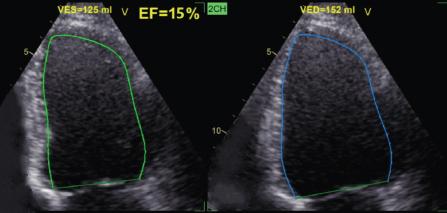

Figure 1